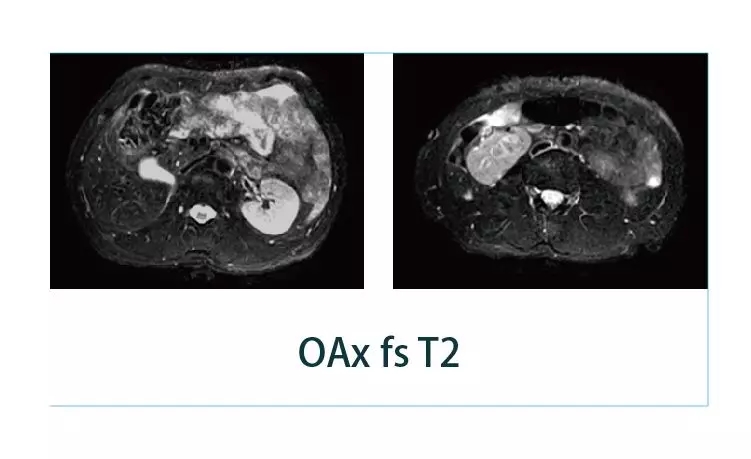

【朗润影像档案】20190301磁共振影像病例结果讨论